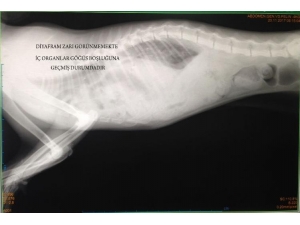

Fıtığı Yırtılan Kedi Sağlığına Kavuştu